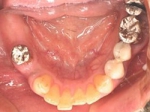

術後(鏡像)

術後口腔内(正面観)もう入れ歯は要らなくなりました。